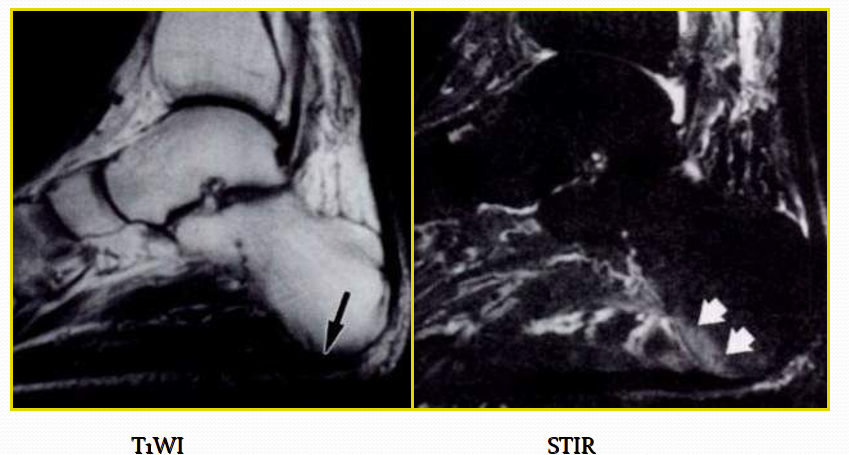

跟腱滑囊炎

足在中立位且轻度跖屈时的矢状面和横断面T2WI是显示滑囊炎和跟腱病变的理想检查方位。当有跟腱前滑囊炎存在时,T2WI上正常跟腱前脂肪消失。合并骨质侵蚀和跟骨后上方骨刺